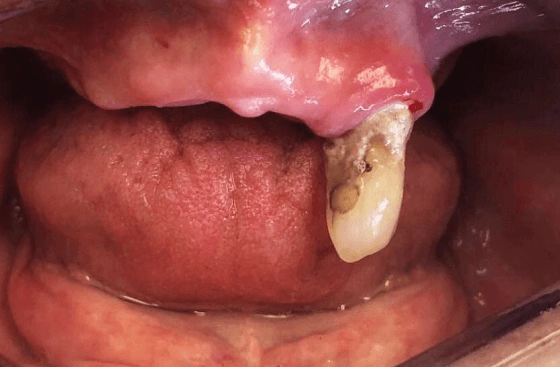

Dental implants are a modern solution for tooth loss, acting as artificial tooth roots. Crafted from biocompatible titanium, these implants are carefully positioned in the jawbone to replace missing teeth. During the process of osseointegration, a remarkable biological phenomenon, the titanium implant fuses with the bone, establishing a solid foundation. This fusion process enables the implant to provide robust support for various dental prostheses, effectively mimicking natural tooth functionality and preserving jawbone integrity. Depending on individual needs, the implant can anchor a single dental crown or support more extensive bridgework for multiple teeth. At Perfect Smile, we understand that every smile has a story. Whether you’re facing the natural changes that come with aging, rebuilding your smile after decay, or seeking restoration from an extraction or accident, our same day implants are here for you. They’re more than just a treatment; they’re a step towards reclaiming the functionality and beauty of your smile, personalised to meet your unique dental needs and aspirations.

To know more, explore the science of tooth implant in our video, showcasing the step-by-step process from initial consultation to final crown placement, and understand the advanced techniques that ensure successful outcomes.